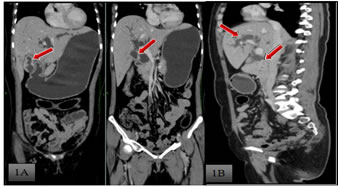

A 45 year old female presented with chief complaints of pain abdomen, non bilious, non projectile vomiting, yellowish discolouration of the skin and eyes with high colouredurine for one month. She also complained of itching over the body. Physical examination revealed presence of icterus and tenderness in the right hypochondrium. A clinical diagnosis of obstructive jaundice was made. No history of any comorbid conditions present with past surgical history of hysterectomy. After routine blood investigations, which revealed increased bilirubin levels, radiological investigations done. Ultrasound of abdomen was performed which showed CBD stricture at the terminal end, grossly thickened gallbladder and peripancreatic lymphadenopathy. Side viewing UGI scopy was done which was normal. To further characterize the ultrasound findings, CECT abdomen was done which showed wall thickening (maximum thickness of 8 mm) noted involving the fundus and body of the gallbladder, irregular and nodular, more on the right lateral aspect with evidence of heterogenous enhancement seen on contrast administration.[Fig-1A] There is no clear fat plane seen between the gall bladder and the liver (segment IV and V), however there is no extension into the liver. Pericholecystic fat stranding seen and minimal pericholecystic fluid seen. Medially it is seen to abut the pylorus of the stomach and first part of the duodenum with no clear fat plane. Posteriorly there are areas of fat stranding seen extending up to the hepatic flexure of the colon. Also there was gross dilatation of the intrahepatic biliary radicles, the common hepatic duct, cystic duct and proximal common bile duct ( measuring 2.4 cm).There is an abrupt tapering at the junction of the mid and distal CBD duct ( just above the intrapancreatic segment) with suggestion of shouldering. [Fig-1B].There is short segment wall thickening (maximum thickness of 4.2 mm) noted in the distal CBD (intrapancreatic segment) for length of approximately 1.7 cm showing enhancement on contrast administration. The distal most CBD and the ampulla were spared. The rest of the intrapancreatic segment of the common bile duct appears normal. This thickening was seen well away from the gall bladder mass. There was no radiological evidence of contiguity noted. MR-Cholangiopancreaticography was done which showed an assymetrical wall thickening involving fundus and body of gall bladder with abuttment of adjacent liver and no infiltration [Fig-2A].Few stranding from the GB wall thickening to the hepatic flexure is seen. Abrupt narrowing with shouldering in the proximal CBD just after insertion of cystic duct and resultant severe upstream dilatation of biliary system [Fig-2B] A pre-operative diagnosis of gall bladder carcinoma with separate CBD involvement was made with possible diagnosis of same primary with skip involvement or synchronous malignancies. Then patient was subjected for pancreaticoduodenectomy [whipples procedure]. Post operative histopathology of the specimens revealed moderately differentiated adenocarcinoma of both gallbladder [Fig-3A] and the distal CBD [Fig-3B]with signet cell formation [15%] [Fig-3C].Margins free of tumour.

Figure 1A: CECT whole abdomen, coronal venous phase shows- Irregular and nodular heterogenous enhancingwall thickening involving the fundus and body of the gallbladder,, more on the right lateral aspect. Medially it is seen to abut the pylorus of the stomach and first part of the duodenum with no clear fat plane. Figure 1B: CECT whole abdomen, sagittal venous phase shows- gross dilatation of the intrahepatic biliary radicles, the common hepatic duct, cystic duct and proximal common bile duct with abrupt tapering at the junction of the mid and distal CBD duct ( just above the intrapancreatic segment) with suggestion of shouldering; Figure 2A: T2 haste MRCP coronal image shows assymetrical wall thickening involving fundus and body of gall bladder with abuttment of adjacent liver and no infiltration; Figure 2B: T2 3D-MRCP shows abrupt narrowing with shouldering in the proximal CBD just after insertion of cystic duct and resultant severe upstream dilatation of biliary system.